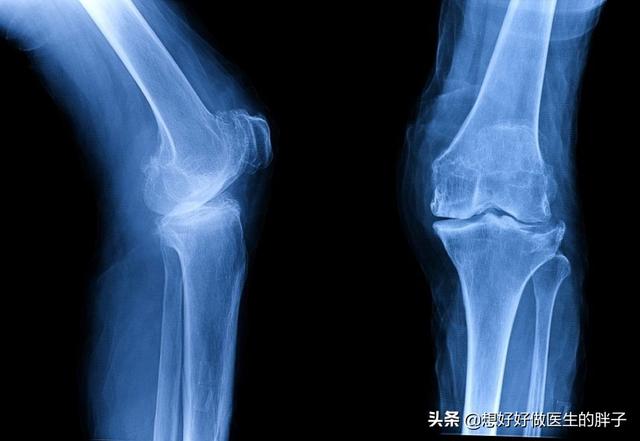

这种下肢力线的异常会增加膝关节内侧关节软骨受到的压力,长此以往会导致软骨的退变,当退变达到一定程度的时候,患者就会出现膝关节的畸形,最常见的是膝内翻畸形,也就是我们常见的o型腿。